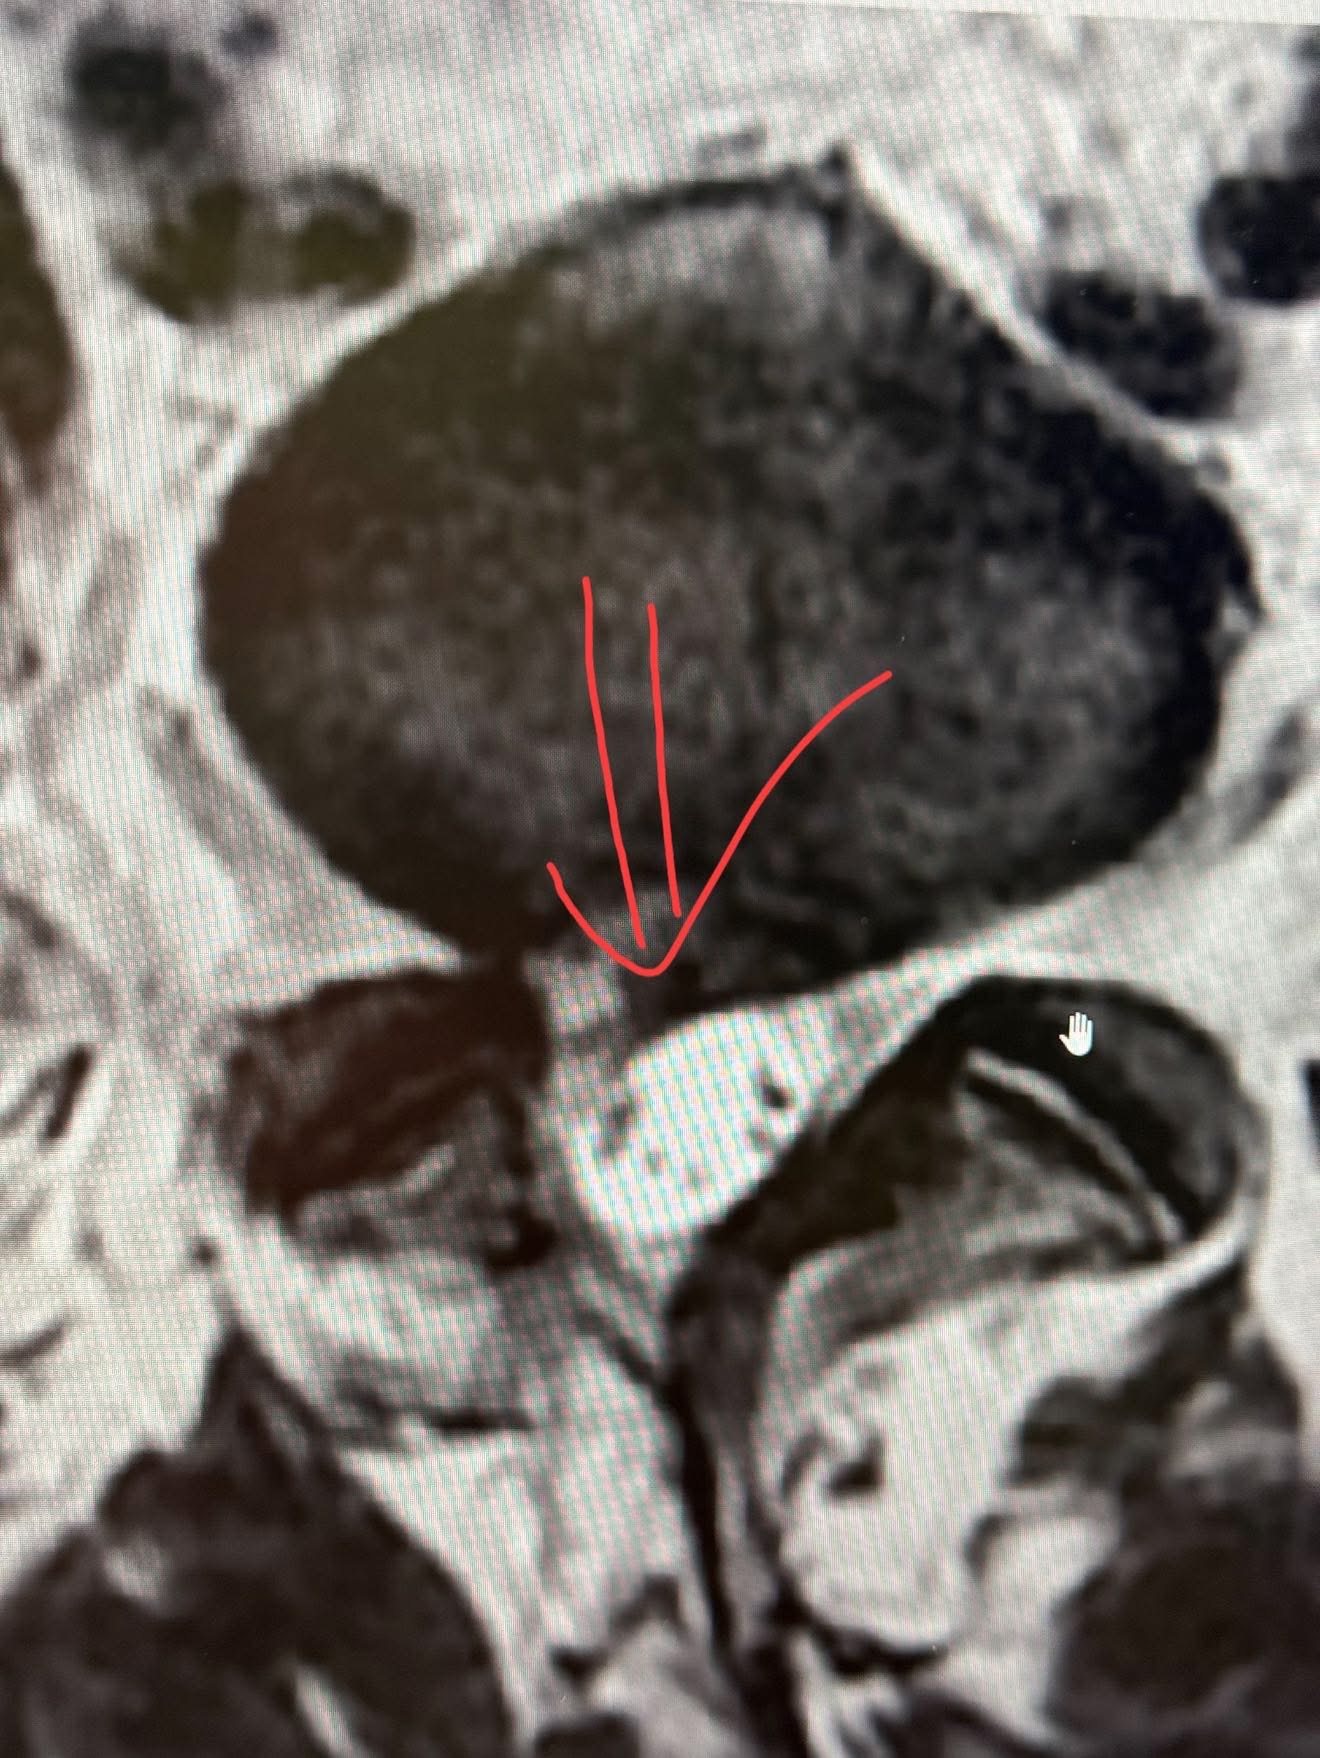

這一拖就是半年以上,她硬是等到了今年(2025年)五月,終於排到MRI,那份影像報告像一張判決書:

L5/S1再度出現巨大椎間盤突出,壓迫神經根。

我仔細翻看她的影像,發現幾個關鍵問題:

• L5/S1再發性椎間盤突出(Recurrent Disc Herniation):術後不到一年再度出現臨床症狀與影像壓迫現象,須排除初次切除不完全或活動過早造成的復發。

• 術後纖維化與瘢痕組織壓迫:也可能是手術後的硬膜外纖維化導致神經卡壓,但從影像來看突出物似偏向軟組織密度而非纖維化。